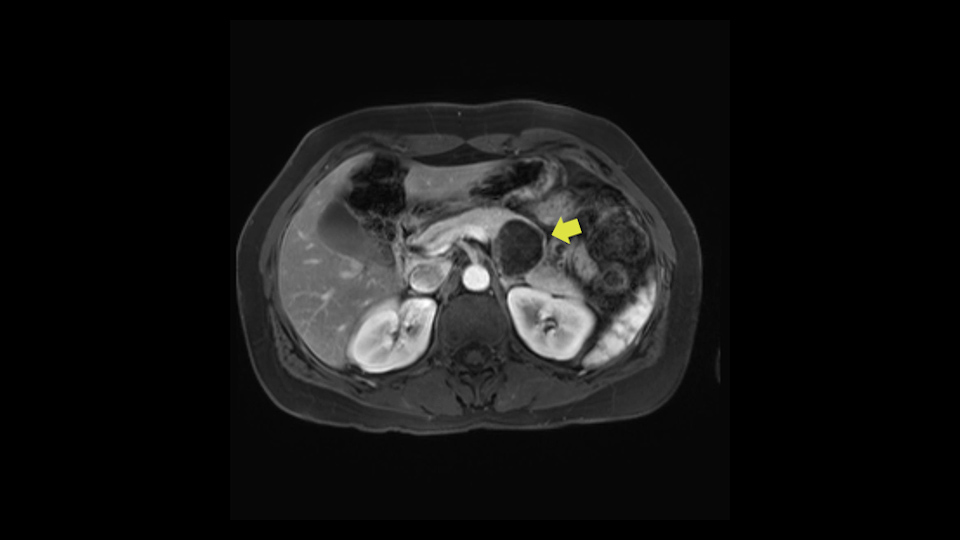

In reviewing this patient’s CT scan, first of all, the lesion is again cystic with a very thin wall. I anticipate that it will be delicate and potentially friable. And therefore the risk of rupture exists and we need to be very careful in how we handle the pancreas and the tumor throughout the procedure.

The lesion itself is quite adjacent to and abuts the splenic vein and therefore we need to anticipate that these two structures will be intimately related and possibly impossible to separate between the two.

The lesion also is quite posterior. While the plane between the cyst and the left adrenal gland is often preserved, we do have to pay attention here so that we remain in the right plane and maintain our margin here. Occasionally in these cases, en bloc adrenalectomy needs to be performed.

The slowing down moments or considerations that I give when I look at the scan and plan my distal pancreatectomy is how far away the tumor is to the portal vein and do I have to formally create a tunnel behind the pancreas on top of the portal vein or do I have to take the pancreas further to the left of the portal vein or the patient’s left of the portal vein. So here I can see that here is the tumor here. I can see that the tumor is a fair way away to the patient’s right and so I will likely not have to take or create the tunnel formally in this procedure. And that speaks a lot to the resection margins. So its important when you’re doing a distal pancreatectomy or any procedure potentially for oncologic reasons to get clearance of the tumor and to take the tumor kind of intact.

So first, I'll show you the scan. Here's the traditional view, where you see the cyst, which is in the body of the pancreas. And you see over here, it's got a quite thick wall. And going a little bit back also, here you see a septation which is very important, because I think a septation is what separates this from, for instance, the pseudocyst of the pancreatitis. And also the location of the cyst you see here, abutting the adrenal gland and going down a bit more, it's also quite close to a bowel loop. So when thinking about this cyst: female, the location in the body of the pancreas, thick wall, septation, and as you can read in history, it was basically asymptomatic, so no signs of pancreatitis. So, this probably all points towards a mucinous cystic neoplasm.

Key features that I look at the imaging are: first I look at the distance between the cyst and the portal vein SMV confluence. So there are guidelines for this, they call the Yonsei guidelines, to decide to do it laparoscopically or open and basically it says that if it’s a cancer, at least a centimeter away from the celiac trunk or the venous confluence. This is a cyst. So maybe you could stretch that a bit, but you don't want to get into trouble there. So for this cyst if you look at it, it's nicely away from the confluence.